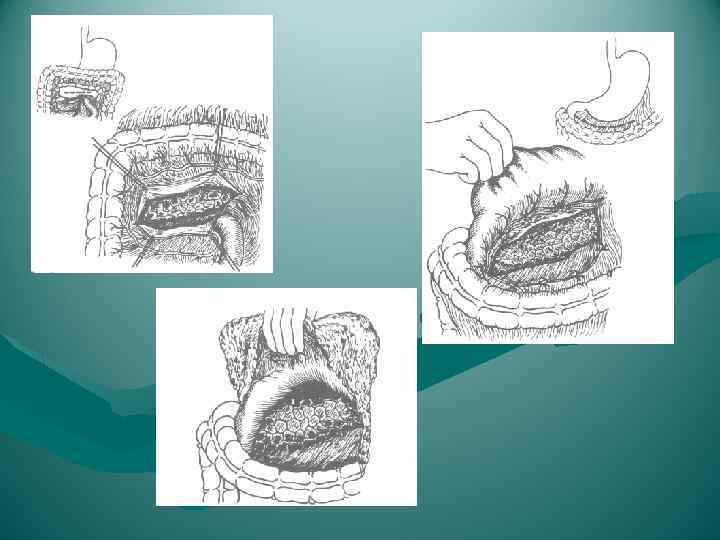

Резекция тела и хвоста поджелудочной железы.

Резекция тела и хвоста поджелудочной железы.